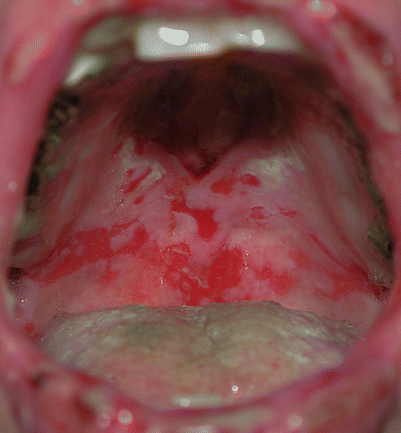

Fig. 33.3

Pemphigus vulgaris. Essentially all patients develop painful oral mucous membrane erosions

The most constant clinical feature of paraneoplastic pemphigus is the presence of intractable stomatitis (Fig. 33.6). The severe stomatitis is usually the earliest presenting sign and after treatment it is the one that persists and is extremely resistant to therapy. This stomatitis consists of erosions and ulcerations that affect all surfaces of the oropharynx and characteristically extend onto the vermillion of the lip. Most patients also have a severe pseudomembranous conjunctivitis with scarring. Esophageal, nasopharyngeal, vaginal, labial, and penile mucosal lesions may also be affected.

Fig. 33.6

Paraneoplastic pemphigus. The characteristic clinical feature is severe intractable stomatitis that extends onto the vermillion of the lip